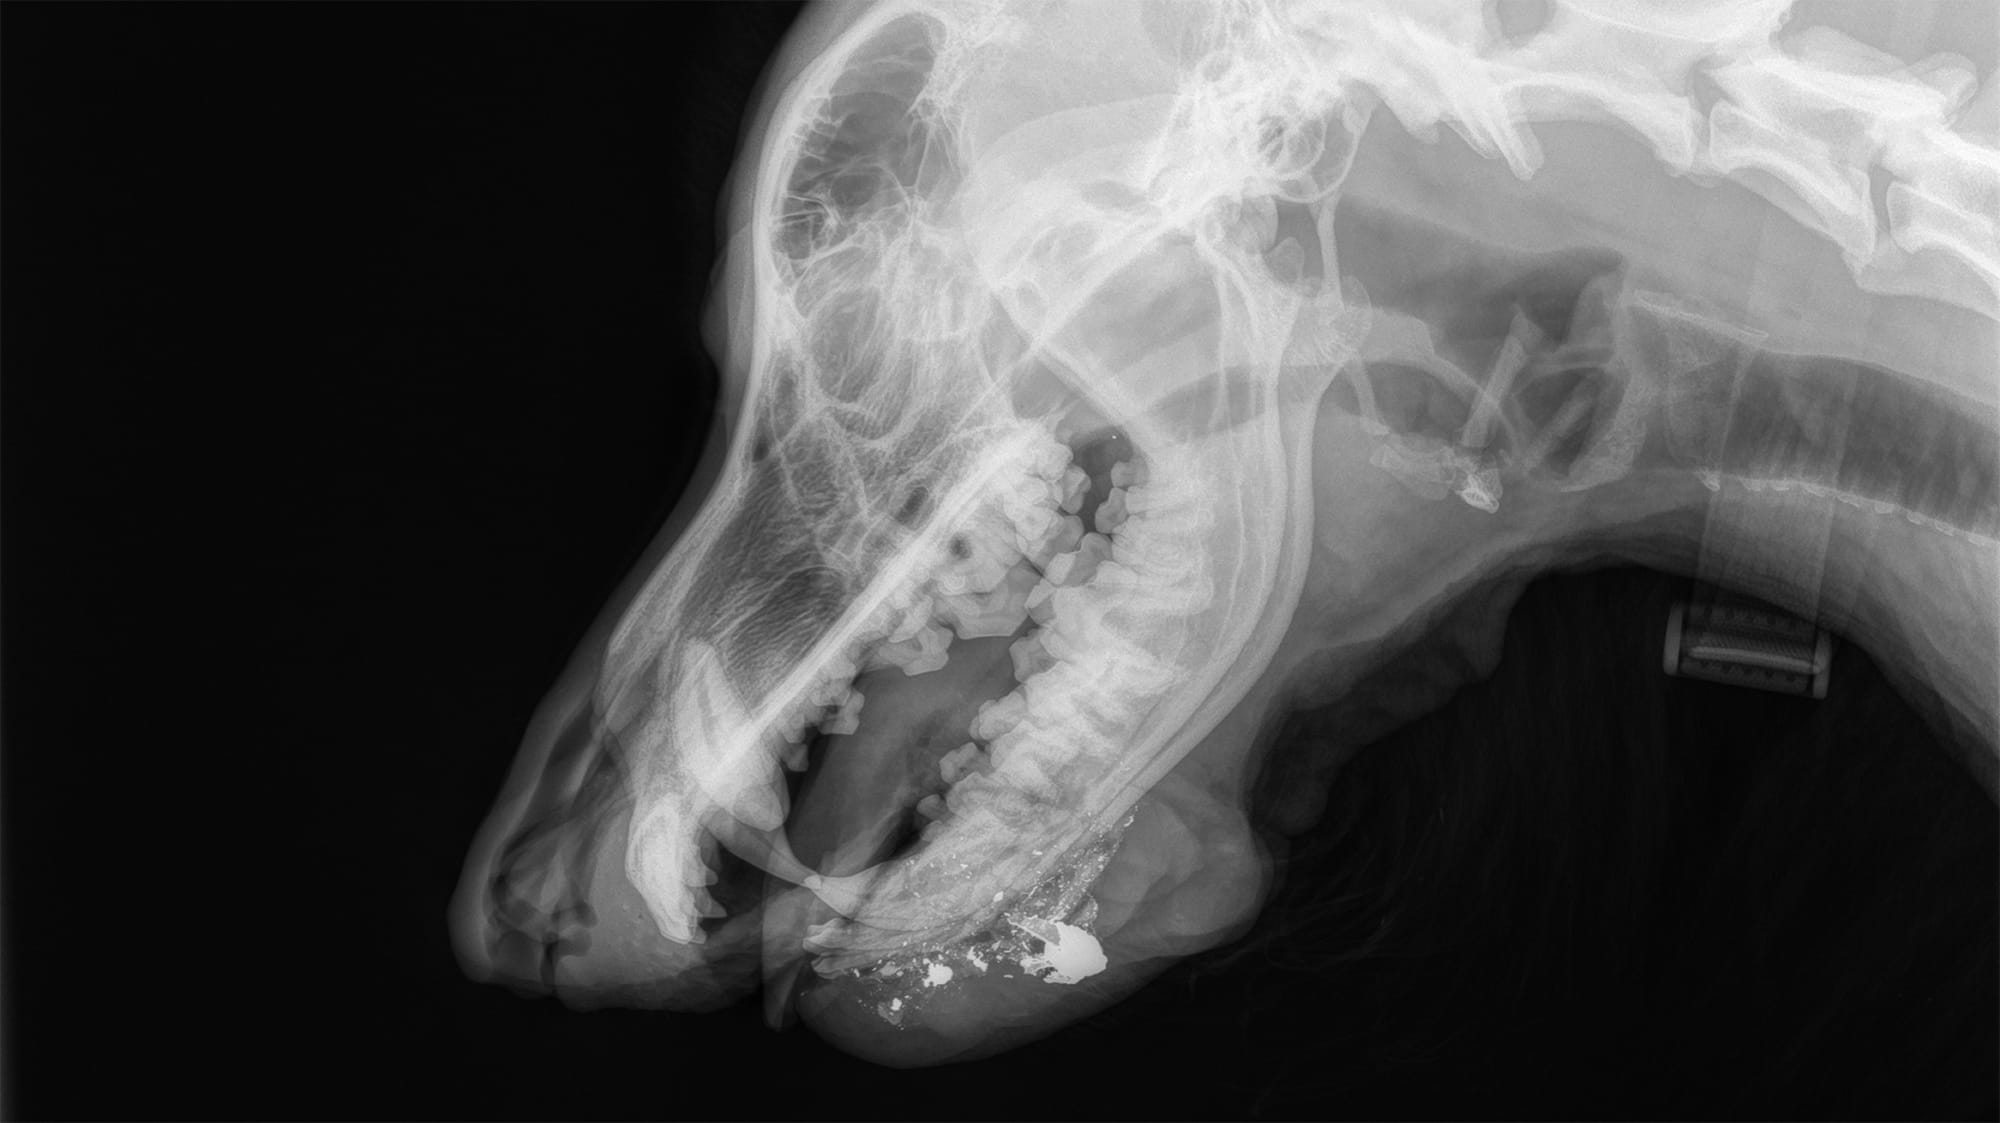

Brutus had been shot in the face and had damage to his canine tooth, the bone of the mandible, and had pieces of bone and bullet throughout his face. Several of his teeth had to be removed, as a well as pieces of bone and bullet, which could cause infection if left untreated. The team removed the injured tissue and affected teeth, then wired his jaw to stabilize his mouth and reconstructed gum tissue. Brutus was under anesthesia for 45 minutes, but his vital signs stayed stable and by 10:30 p.m., the surgery was complete and he was resting.